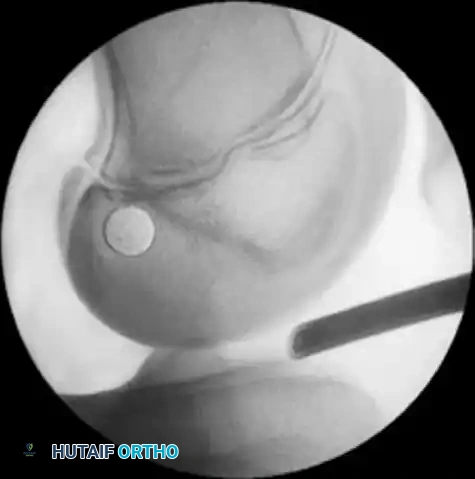

- Fluoroscopic Guidance: With the C-arm in the lateral position, adjust the limb to maintain the perfect lateral view.

- Guidewire Placement: Place the point of the guidewire over the lateral femoral condyle. The correct entry point corresponds to the ACL footprint: approximately one-fourth of the distance from posterior to anterior along Blumensaat's line, and one-fourth of the distance down from Blumensaat's line.

- Drilling the Epiphysis: Using a free-hand technique under C-arm guidance, introduce the guidewire 2 to 3 mm into the femoral epiphysis.

- Crucial Step: Do not angulate the pin anteriorly or posteriorly; keep it strictly perpendicular to the femur in the coronal plane.

- Rotate the C-arm to the AP plane to confirm the guidewire is not angulated superiorly (which would violate the physis) or inferiorly (which would breach the articular cartilage).

- Joint Entry: Drive the guidewire across the femoral epiphysis, perpendicular to the femur and distal to the physis. Arthroscopically visualize the wire entering the intercondylar notch. It should enter the joint 1 mm posterior and superior to the center of the anatomical ACL footprint.